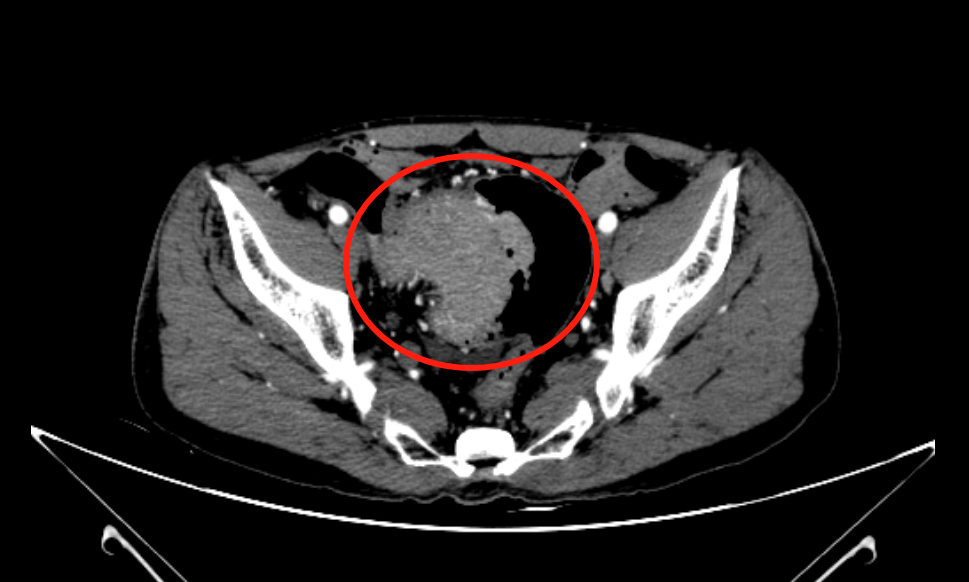

通过进一步检查发现,冯先生肠道内 多发占位,考虑 肿瘤性病变。其中升结肠见环腔肿物基本占据整个肠腔,直乙交界处巨大肿物侵犯膀胱。

直肠肿瘤侵犯膀胱

之前的肠镜活检结果也提示,两个部位肿物均为恶性肿瘤。万幸的是,冯先生身体其他远隔部位和其他脏器未见到转移肿瘤的病灶。